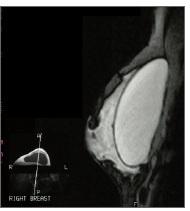

IMPLANTS MAMMAIRES et ruptures silencieuses, l'IRM n'est pas infaillible –